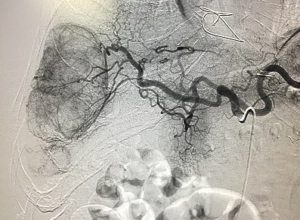

As the inventors of angioplasty and the catheter-delivered stent, which were first used in the legs to treat peripheral arterial disease, interventional radiologists pioneered minimally invasive modern medicine. KIC’s interventional radiologists are board-certified physicians who specialize in minimally invasive, targeted treatments. We offer the most in-depth knowledge and least invasive treatments available coupled with diagnostic and clinical experience across all specialties. Using X-ray, MRI and other imaging technologies to advance a catheter in the body, usually in an artery, we treat patients at the source of the disease, non-surgically.